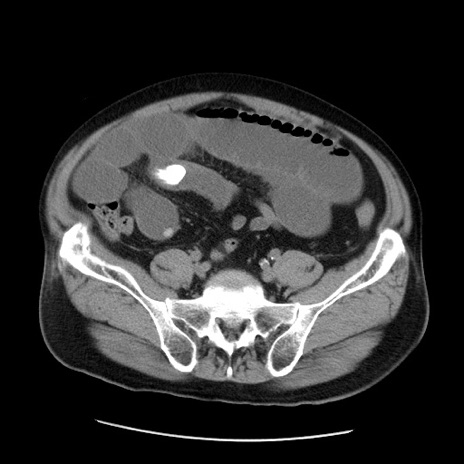

症例20(横断像)

【症例】 60歳代男性

【主訴】 腹部膨満、嘔吐

【現病歴】5日前頃より倦怠感を認め食事量減少し4日前の朝嘔吐、食事摂取困難となった。 3日前近医受診し点滴施行され整腸剤などを処方された。 当日他院を受診し、腹部膨満著明、炎症反応の上昇(CRP10.8、WBC11200)あり、紹介受診となる。

【身体所見】 意識JCS1 受け答えがはっきりしないBP 111/57mHg、 P 67bpm、、BT35.2°C、SpO2 97%(RA)、 腹部:膨隆、打診で鼓音あり、全体的に圧痛有り、腸蠕動音(-)、反跳痛ははっきりせず。

【データ】WBC 11400、CRP 14.20